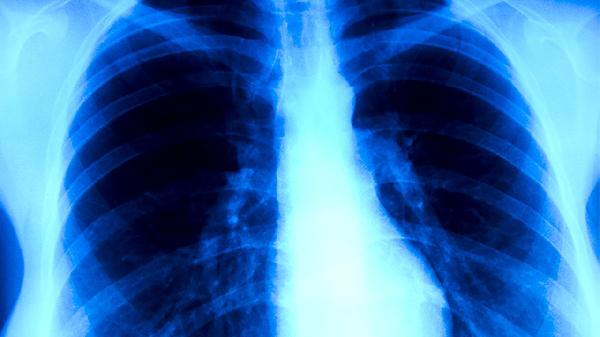

1、肺癌

消癌平口糖浆可用于肺癌的辅助治疗,尤其适用于气阴两虚型患者。该药物能缓解咳嗽、痰中带血、胸痛等症状,常与化疗联合使用减轻毒副作用。需注意用药期间可能出现轻度胃肠反应,应在医生指导下规范使用。